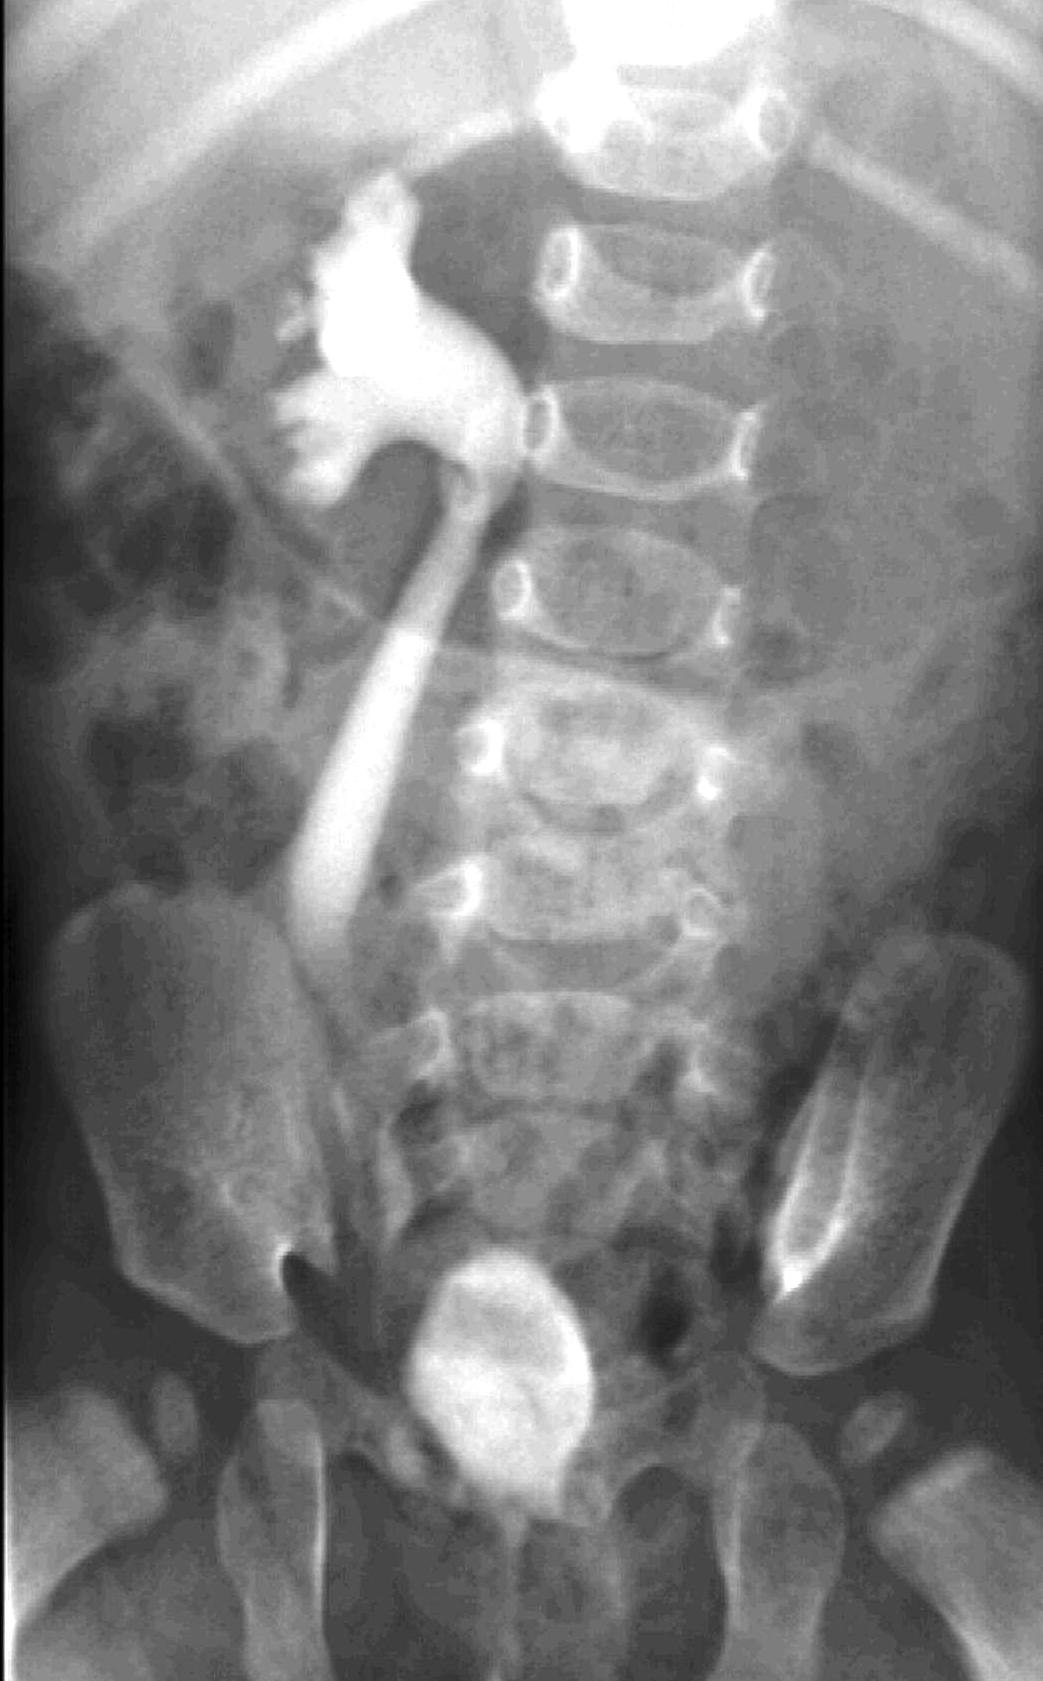

During X-ray examination the contrast material does not progress to the jejunal loops or it shows a “corkscrew” sign on the right side of the vertebrae as it piles up in the twisted intestinal loops.

Image

15. Contrast material empties the stomach slowly, small intestines are found on the right side of the abdomen. Malrotation-volvulus.